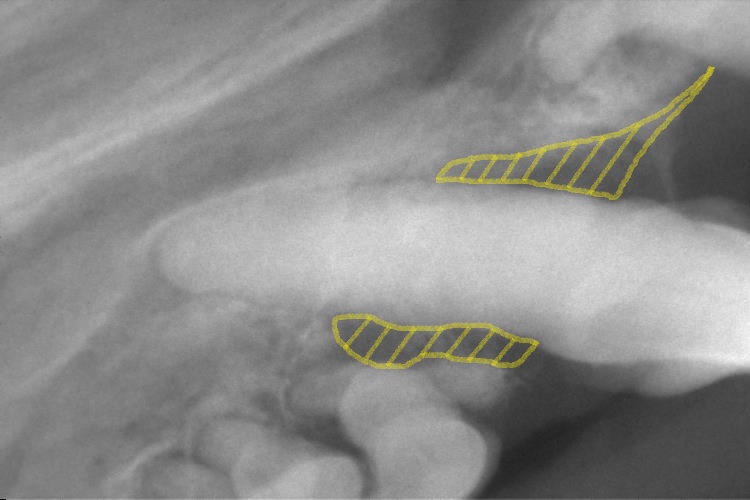

歯科レントゲン検査

矢印の歯は、乳歯の歯根です。吸収されずに残っていました。(黄色矢印)

また他の歯は歯周病により歯槽骨が溶けてぐらついていました。

黄色の斜線部分(写真左)も歯周病により歯根部の周りの歯槽骨が溶けています。

他の歯でもこのような症状がみられました。